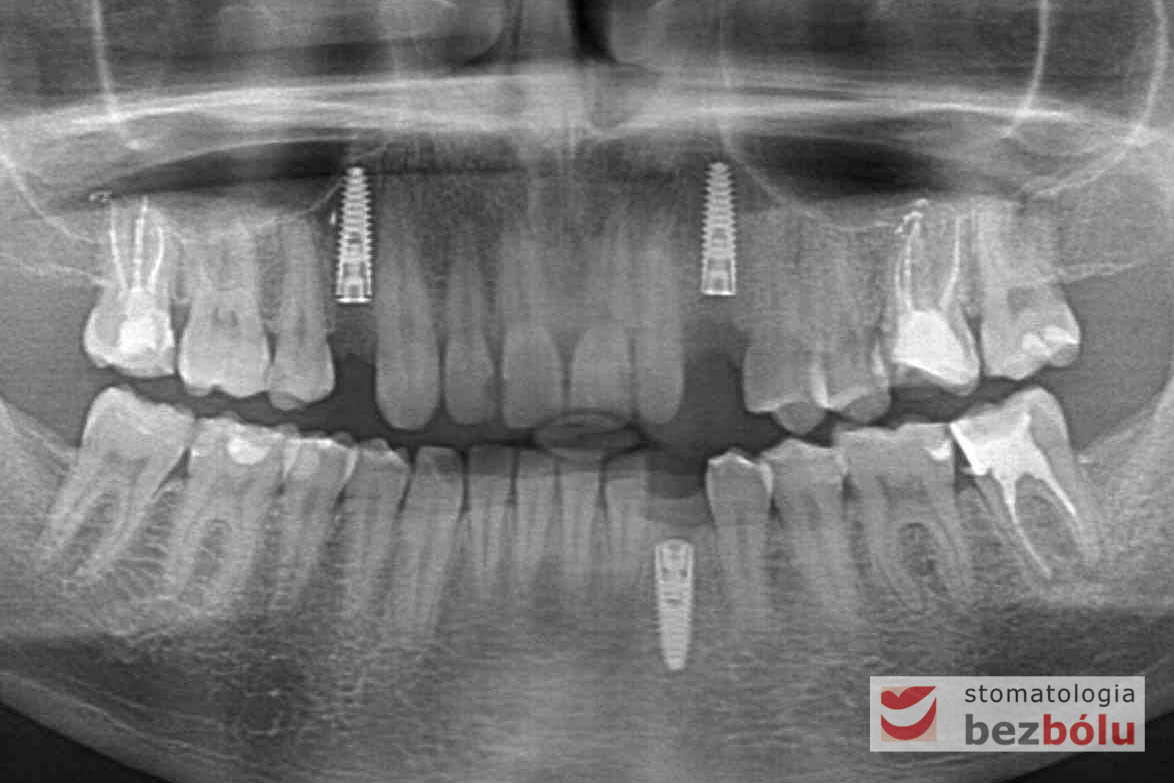

Po zakończeniu procesu gojenia wyrostka zębodołowego, wykonano diagnostykę radiologiczną z zastosowaniem tomografii wiązki stożkowej (CBCT) w celu oceny ilości oraz jakości tkanki kostnej, zarówno w miejscach poekstrakcyjnych, jaki i w pozycji górnego prawego przedtrzonowca. Ponadto pobrano wyciski, oddające sytuację kliniczną w jamie ustnej pacjenta, który zdecydował się na metodę implantacyjną, wykorzystującą nawigację komputerową, z zastosowaniem protokołu MGuide firmy MIS. Procedura ta polega na cyfrowym zaplanowaniu pozycji implantów, a następnie wykonaniu w technice druku 3D szablonu chirurgicznego.Taka metoda pozwala wyeliminować konieczność odwarstwiania płatów, zmniejszając przy tym pozabiegowe dolegliwości. Usprawnia jednocześnie pracę operatora, dokładnie pozycjonując wszczep w pożądanej pozycji. Kolejnym krokiem było przesłanie skanów modeli gipsowych oraz tomografii do siedziby MCenter w Berlinie, gdzie wysoko wyspecjalizowani technicy, dysponujący najnowszą technologią cyfrową, precyzyjnie wykonali szablony nawigacyjne, stosowane podczas zabiegu implantologicznego.

Procedurę chirurgiczną rozpoczęto od sprawdzenia przylegania szablonów do zębów pacjenta oraz znieczulenia miejscowego. W kolejnym kroku, przy pomocy specjalnie przeznaczonego do tego celu zestawu wierteł, wypreparowano krążki dziąsła punktowo odsłaniające kość a następnie poprzez tuleje prowadzące, z najwyższą precyzją, opracowano łoże implantu. Kulminacyjny moment zabiegu, czyli wprowadzenie wszczepów MIS C1 również odbyło się poprzez szablon, gwarantując precyzyjną lokalizację implantów. Zwieńczeniem całej procedury było przyszycie uprzednio wypreparowanych krążków śluzówkowo-okostnowych. Tuż po zabiegu, celem weryfikacji poprawnej pozycji implantów, wykonano zdjęcie ortopantomograficzne. Podczas wizyt kontrolnych, pacjent nie skarżył się na żadne dolegliwości bólowe, nie wystąpił obrzęk, a zreponowane we właściwych miejscach fragmenty dziąsła nie wykazywały oznak martwicy, co świadczyło o ich ponownym ukrwieniu i wgojeniu się. Wszystkie te przesłanki jasno wskazują na skuteczność zastosowania techniki komputerowej nawigacji w implantologii.